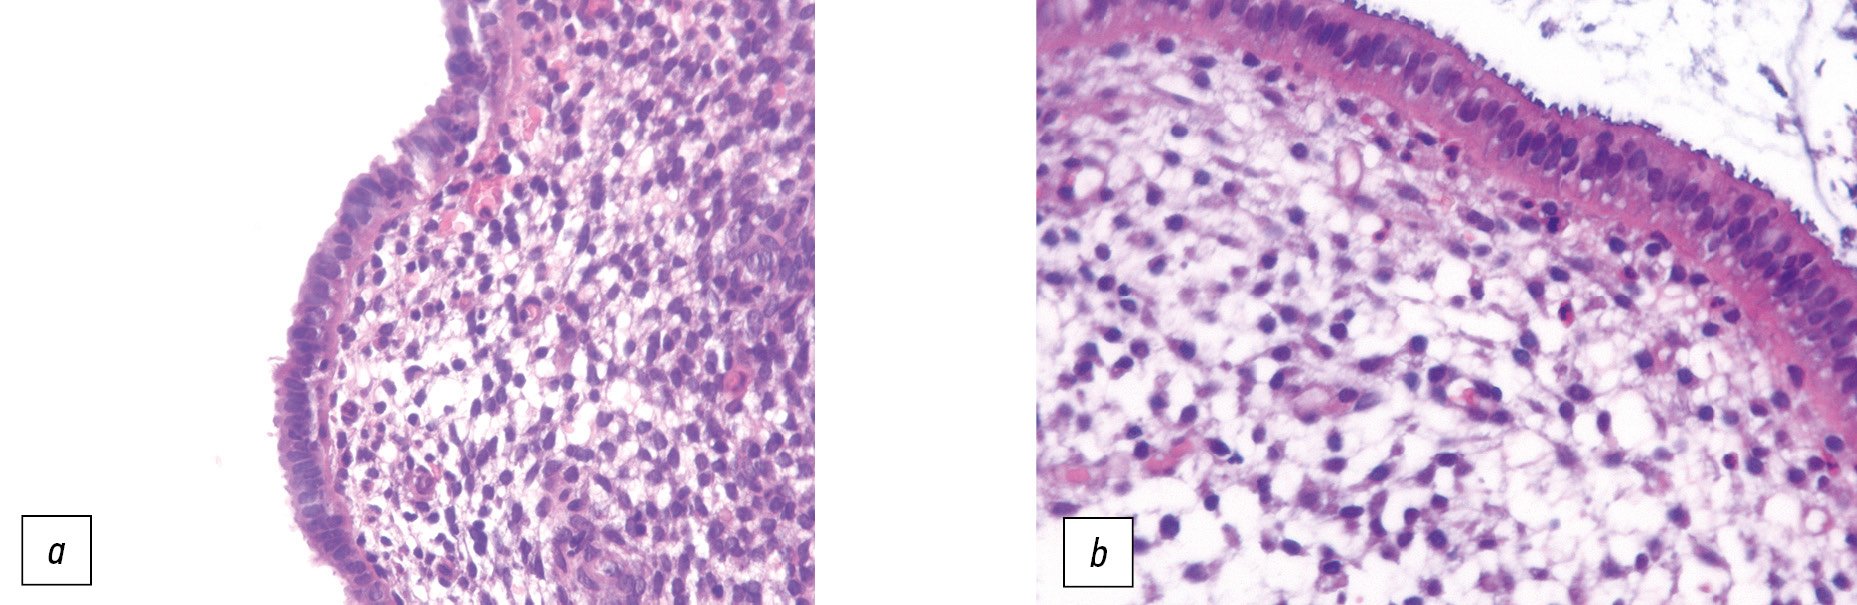

При анализе данных патоморфологического исследования до оперативного вмешательства в 1-й группе зафиксировано, что у 9 пациенток (28,3%) эндометрий соответствовал средней стадии фазы секреции, у 17 (55,5%) — поздней стадии фазы пролиферации, у 4 (16,2%) — ранней стадии фазы секреции. Морфометрия биоптатов слизистой матки свидетельствует о снижении способности поверхностного эпителия к формированию люминальных выростов. У 9 наблюдаемых (30,01%) обнаружены развивающиеся и зрелые пиноподии, занимающие 70% клеток апикальной мембраны, что согласуется с исследуемой фазой менструального цикла. У 2 исследуемых (6,66%) определялись развивающиеся пиноподии в 10–15% клеток, что указывает на задержку секреторной трансформации эндометрия и, как следствие, своевременного открытия окна имплантации (рис. 1, а). Люминальные выросты поверхностного эпителия эндометрия у 19 пациенток (63,33%) отсутствовали.

Рис. 1. Пиноподии эндометрия у пациенток с серозной цистаденомой яичников: a — на поверхности эпителия до операции наблюдаются развивающиеся пиноподии (10–15%); b — через 6–12 мес после операции на поверхности эпителия имеются зрелые пиноподии (70–90%).

Fig. 1. Pinopodiums of the endometrium in patients with serous ovarian cystadenoma: a — developing pinopodiums are observed on the surface of the epithelium before surgery (10–15%); b — 6–12 months after the operation, there are mature pinopodiums (70–90%) on the surface of the epithelium.

Через 6–12 мес после оперативного вмешательства у 17 пациенток (56,66%) с серозной цистаденомой отмечено увеличение количества биоптатов, идентифицируемых как средняя стадия фазы секреции (p ≤0,05). Поздняя стадия фазы пролиферации эндометрия выявлена у 7 пациенток (23,33%) этой группы, ранняя стадия лютеиновой фазы — у 6 (20,01%). При определении процентного количества клеток, содержащих на своей апикальной поверхности люминальные выросты, установлено статистически незначимое увеличение их числа. Зрелые пиноподии зафиксированы у 16 пациенток (51,34%), клетки занимали 70–90% поверхностного эпителия (рис. 1, b), у 6 обследуемых (20,0%) отмечены регрессирующие пиноподии в 20% клеток апикальной мембраны, у 8 пациенток (26,66%) куполообразные выросты не визуализировались, что ассоциировано с нарушением имплантационных свойств эндометрия.